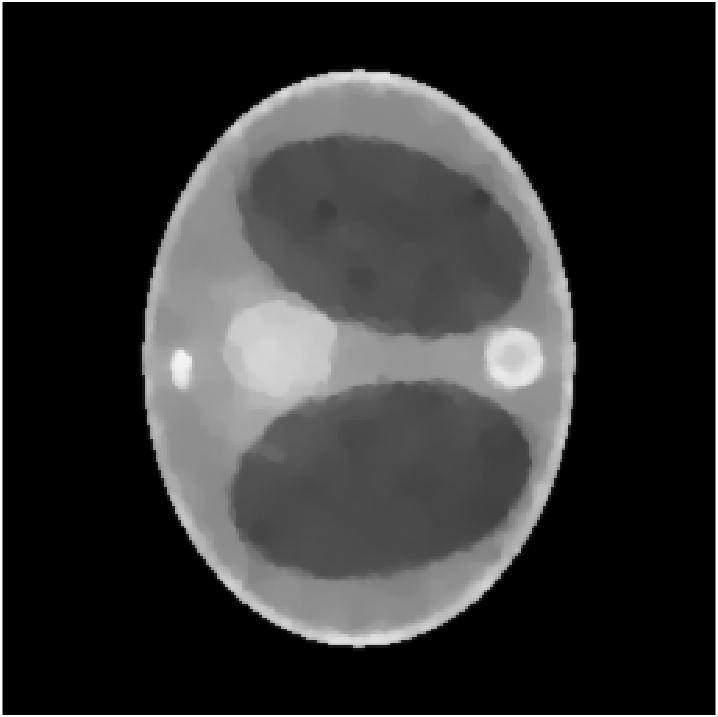

We assume to measure a total of photons and compute synthetic data from eq. 11 for a phantom electron density modeling a transversal slice of a human thorax. The phantom (see fig. 2(b)) consists of characteristic functions of ellipses of different sizes and opacities and is a modified version of an earlier phantom which was used in [12]. It is 28.4 cm resp. 21.3 cm wide at its largest and smallest diameters and its gray values are chosen as electron densities of materials typical in a human thorax [15, 3, 30].

In the reconstruction, a suitable choice for the regularization parameter is computed by the L-curve method. In fig. 3(e) we see that a reconstruction of the electron density from works well and the TV penalty term reduces the effects from the Poisson noise sufficiently. However, adding the component (fig. 3(f)) to the spectrum distorts the reconstruction. Due to the enormous noise level brought into the model by the component , the TV-regularized solution suffers from bad quality. Details are less visible or harder to localize and intensities of the different regions are altered complicating material recognition.